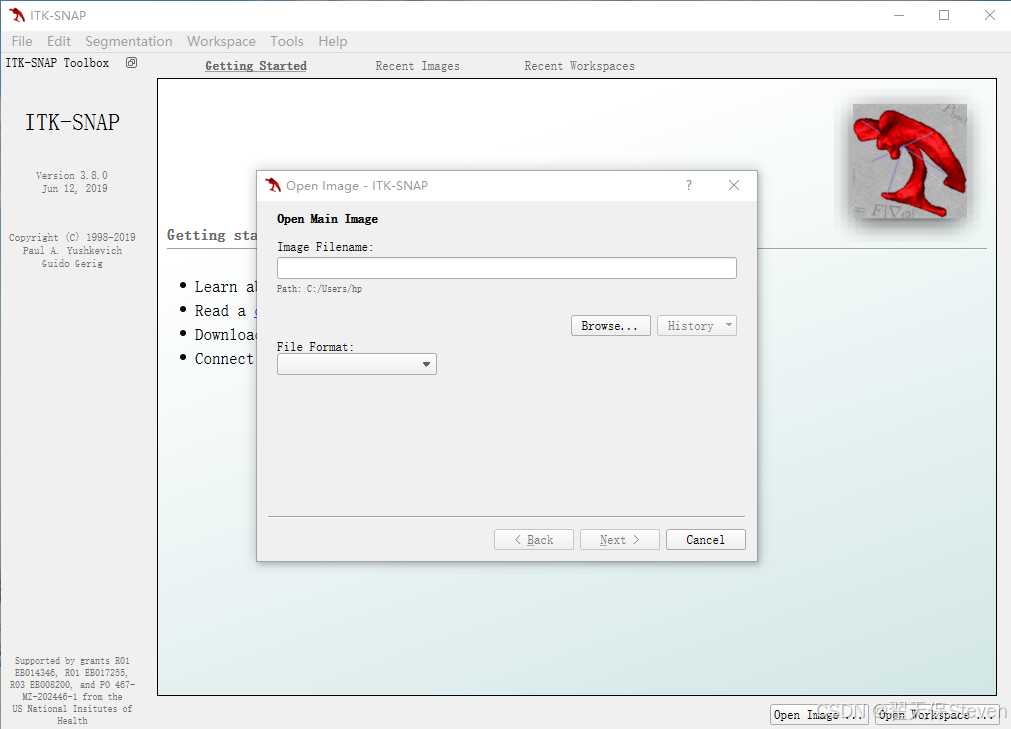

2)打开ITK-SNAP,点击File,选择Open Main Image,这里打开的是主图像。